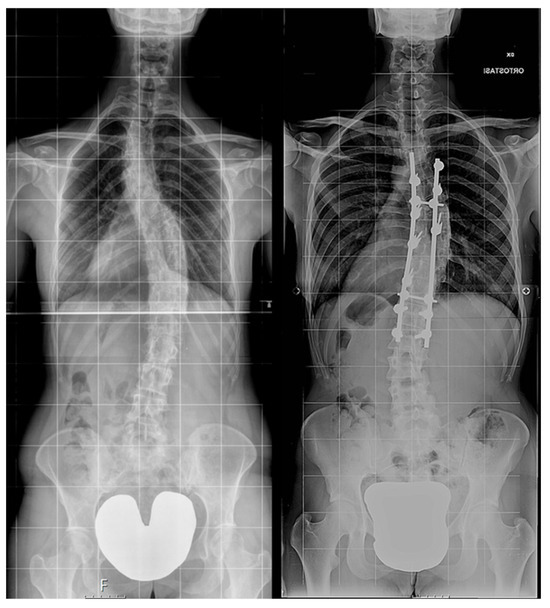

Then, patients were further subdivided into two groups depending on the surgical procedure performed (Figure 2):

Figure 2. Examples of non-instrumented (left) and instrumented (right) long-term X-ray.